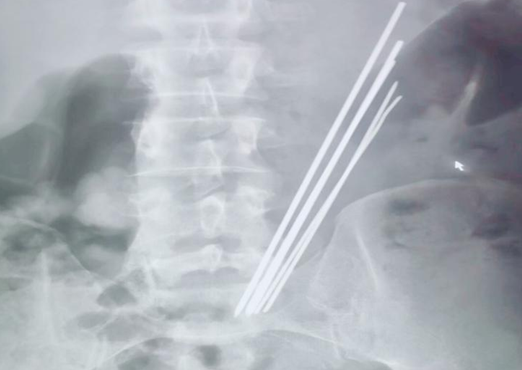

2019年10月30日,延安大學(xué)咸陽(yáng)醫(yī)院內(nèi)鏡中心一如既往,仍是一番忙碌景象。電話響起,我院普外科二病區(qū)來(lái)電,科室就診了一位特殊患者,又一例消化道異物,與此前不同的是,這位病患的異物已吞入達(dá)3年之久,間斷腹痛,未予重視及治療,近來(lái)因臍周疼痛逐日加重,就診于多家醫(yī)院,無(wú)一例外,均建議手術(shù),患者及家屬疲于奔波,最終無(wú)奈接受,遂來(lái)我院要求行手術(shù)治療。主管醫(yī)師接診后積極詢(xún)問(wèn)病史,完善相關(guān)檢查,令人訝異的是,3年時(shí)間異物依舊潴留于胃腔之中,腹平片提示為多個(gè)長(zhǎng)條狀金屬異物,棘手之處在于患者拒絕提供關(guān)于異物的詳細(xì)信息。聽(tīng)聞我科上次胃內(nèi)異物取出報(bào)道,主管醫(yī)生抱著試試看的態(tài)度打通了內(nèi)鏡室的電話。

李恒副主任醫(yī)師詳細(xì)了解上述情況后,立即與內(nèi)鏡中心麻醉師張玉河醫(yī)生溝通,暫時(shí)無(wú)法確認(rèn)異物是否嵌頓入胃壁,以及其嵌入深度,普通胃鏡的刺激極有可能加劇患者痛苦,為異物取出造成阻礙,無(wú)痛胃鏡相對(duì)而言,患者痛苦較小,避免了配合度不高等情況,但與此同時(shí),因異物存留于胃腔內(nèi)時(shí)間較長(zhǎng),考慮金屬質(zhì)地,且數(shù)量較多,操作過(guò)程中必然會(huì)面臨很多棘手問(wèn)題,并發(fā)呼吸困難、大出血的風(fēng)險(xiǎn)。消化內(nèi)科一病區(qū)李主任和麻醉醫(yī)師張玉河認(rèn)真翻閱患者相關(guān)信息,制定出嚴(yán)謹(jǐn)、詳盡的治療方案。征得患者及家屬同意后,又一場(chǎng)攻堅(jiān)戰(zhàn)展開(kāi)了......進(jìn)鏡至胃腔,可見(jiàn)5個(gè)長(zhǎng)條形金屬異物滯留,表面光滑,粘液附著,抓取難度非常之大,需在胃腔內(nèi)不斷調(diào)整方向,確保異物以豎直狀態(tài)隨胃鏡緩慢退出,避免異物通過(guò)食管及口腔時(shí)造成的二次損傷,經(jīng)過(guò)反復(fù)不懈努力,最終異物全部安全取出,長(zhǎng)條狀金屬異物最長(zhǎng)達(dá)16cm左右?;颊呒覍匐y掩興奮之情,不停的念叨著“謝謝,謝謝”,內(nèi)鏡下的異物取出讓他們的親人免受手術(shù)之苦,同時(shí)也減輕了經(jīng)濟(jì)負(fù)擔(dān)。